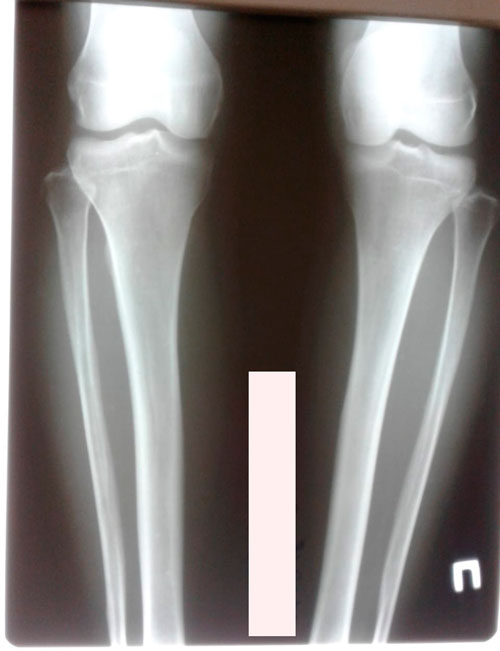

Дата операции- 18.12.2018г.

Дата снятия аппаратов - 05.03.2019г.

Срок сращения - 75 дней.

Через три недели пойду на рентген и вышлю в клинику. И исходя из результатов буду уже покупать билеты в Павлодар, для снятия аппаратов. Я очень рада, что проперировалась. Об этой операции мечтают тысячи женщин. Хочу Вам сказать, милые дамы, без приложения усилий любая мечта так и остаётся мечтой. Здесь, как и в любом другом деле, нужно ставить цель и достигать её. Я понимаю вопрос всегда упирается в финансы. Но ради осуществления своей заветной мечты под названием "красивые и здоровые ножки" можно отказаться от нового Айфона и других маловажных вещей. Ведь здоровье на первом месте. При кривизне ног коленный сустав изнашивается преждевременно и к 40 годам начнёт беспокоить боль в коленях. Об этом я узнала недавно и понимаю почему мама жалуется на колени. Если смогу убедить её, то тоже приведу её на операцию, ей 59 лет. Хочу, чтобы она прожила долго, сохраняя подвижность до старости, чтобы она вела активный образ жизни.